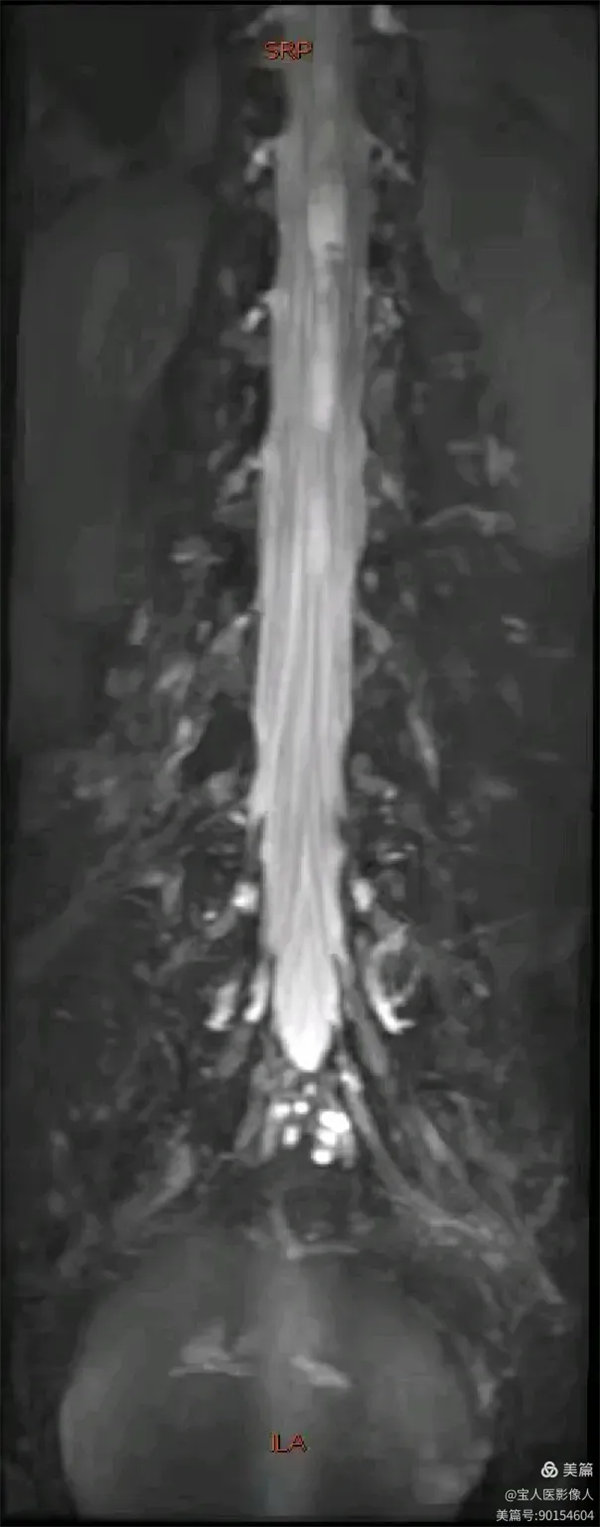

容积成像和最大密度,显示腰段脑脊液正面图。

最大密度正面图,显示腰段脑脊液(高信号),其内的马尾神经以及腰神经(线状稍低信号)。